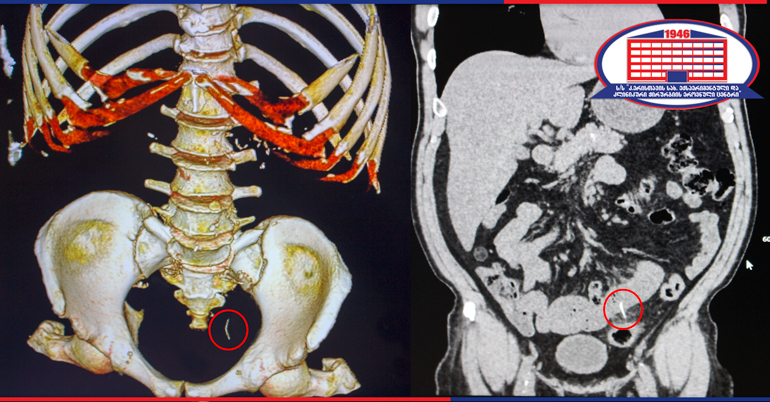

Радиолог клиники, Ираклий Гигиадзе отметил, что тонкий кишечник был поврежден инородным телом. Неизвестное инородное тело исходило из кишечника в брюшную полость. Пациенту провели лапароскопию. Было найдено и удалено инородное тело, а поврежденную область тонкого кишечника зашили.

Инородным телом, которое удалили из тонкого кишечника пациента, оказалось металлическая проволока (проволочная мочалка для мытья посуды), размер которой составлял 4 см и попал в желудочно-кишечный тракт с пищей.